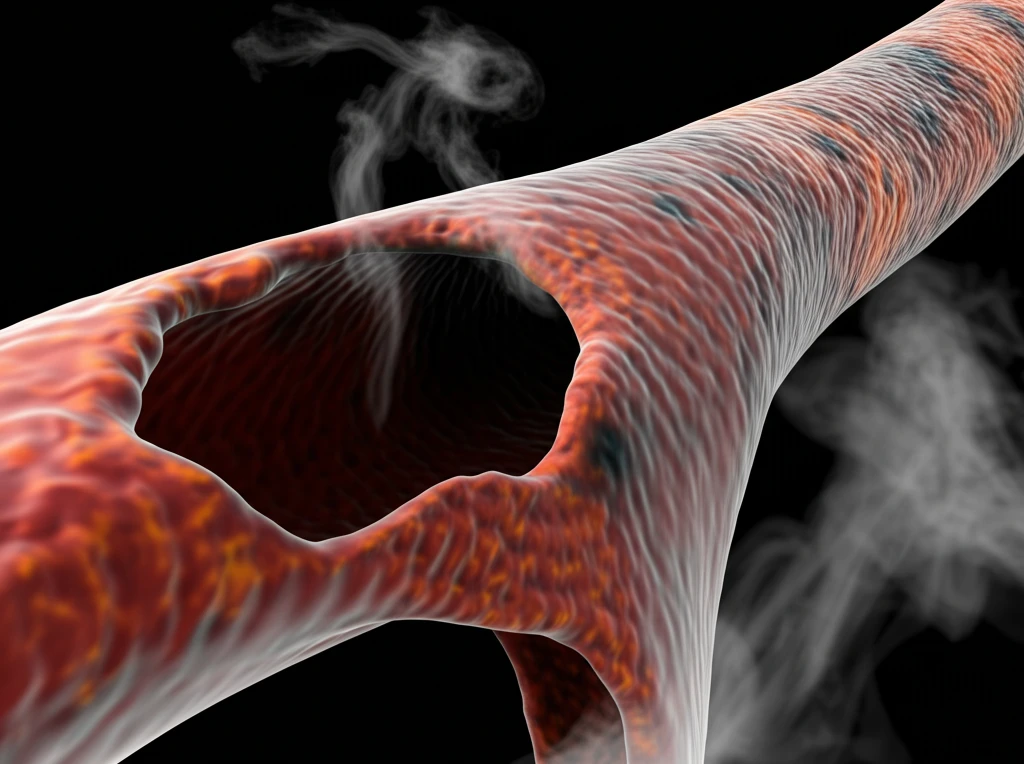

기관지염은 숨쉬는 데 중요한 역할을 하는 기관의 내벽에 염증이 생기는 질환입니다. 기관은 폐로 공기를 전달하는 통로인데, 이 부분에 염증이 생기면 여러 가지 호흡기 증상이 나타날 수 있습니다. 기관지염은 크게 급성 기관지염과 만성 기관지염으로 나뉘며, 각각의 원인과 진행 과정, 치료법이 다릅니다. 급성 기관지염은 보통 바이러스 감염으로 인해 발생하고, 만성 기관지염은 장기간의 기관지 손상으로 인해 생기는 경우가 많습니다.

반면, 만성 기관지염은 기관지가 장기간에 걸쳐 손상되어 발생하는 질환으로, 주로 흡연이나 유해 물질 흡입이 원인입니다. 만성 기관지염은 기침과 가래가 3개월 이상 지속되고, 이러한 증상이 2년 이상 반복되는 경우를 말합니다. 만성 기관지염은 폐 기능 저하를 동반할 수 있으며, 심한 경우 만성 폐쇄성 폐질환(COPD)으로 이어질 수 있습니다.

만성 기관지염은 장기간의 기관지 손상으로 인해 발생하며, 흡연이 가장 큰 위험 요인입니다.